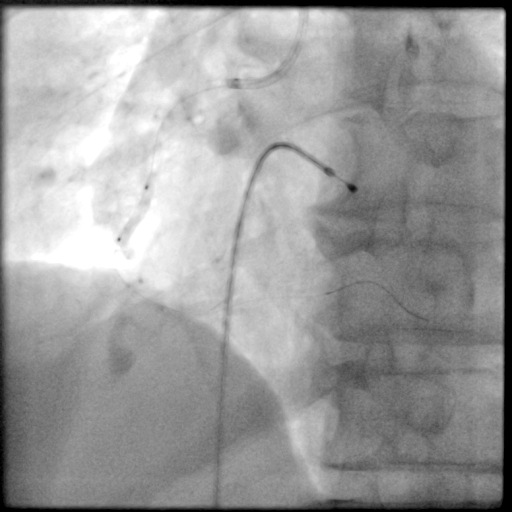

PCI过程-DES植入

由远及近依次送4.0X23mm、4.0X29mm、4.0X13mm DES至病变处串联释放。

PCI过程-支架后造影